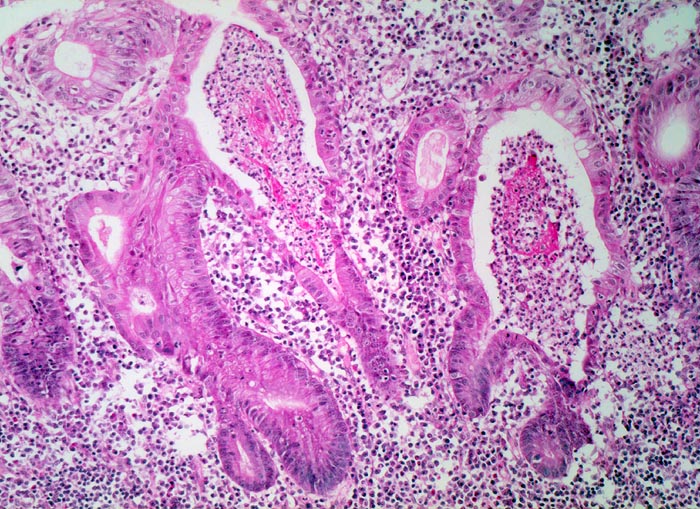

Mikroskopisch findet sich je nach Entzündungsaktivität eine mehr oder weniger ausgeprägte diffuse Verdichtung des lymphoplasmazellulären Entzündungsinfiltrates mit Beimischung von Granulozyten in Form einer Kryptitis oder von Kryptenabszessen. Bei einer stark aktiven Entzündung finden sich zusätzlich Erosionen und Ulzera mit Ausdehnung der Entzündung über die Mukosa hinaus in die Submukosa oder in noch tiefere Schichten bei hochflorider Kolitis. Die Kryptenarchitektur ist gestört, die Anzahl der Krypten und der Becherzellen vermindert. In der Regeneratphase finden sich zahlenmässig reduzierte und verkürzte Krpyten mit normaler Anzahl Becherzellen. Meist bleibt eine leichte Verdichtung der Entzündungszellen in der Lamina propria bestehen.

Unregelmässig geformte und verzweigte Krypten (Kryptenarchitekturstörung).

Krpyten enden deutlich oberhalb der Lamina muscularis mucosae (Kryptenatrophie).

Verminderte Schleimbildung und Becherzellverlust.

Basal betonte Plasmozytose und Infiltrate neutrophiler Granulozyten.

Ansammlungen neutrophiler Granulozyten in Kryptenlumina (=Kryptenabszesse) und Infiltrate von neutrophilen Granulozyten im Kryptenepithel (=Kryptitis).